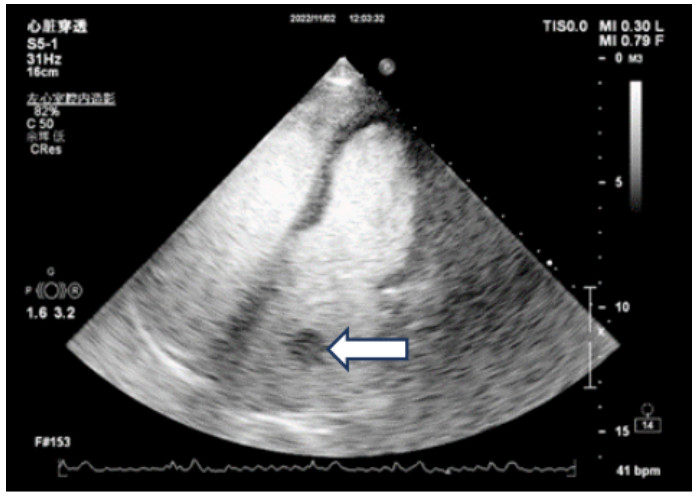

既往史:有高血压病史10年余,规律降压治疗,未监测血压。房颤病史2年余,2022年11月在本院超声心动图显示左心房见一不均质低回声团,位置随心动周期漂动(17 mm×16 mm)”(见图 1),左房前后径40 mm,左右径46 mm,上下径70 mm。LVEDD 39 mm,LVEF:60%。二尖瓣E峰0.92 m/s,最大压差3.39 mmHg(1 mmHg=0.133 kPa)。反流面积3.8 cm2,二尖瓣口频谱呈单峰。舒张期二尖瓣口前向血流,E < A,无舒张功能不全。进一步行经心脏超声造影提示:Flash后,左心室心腔内团块未见明显灌注(见图 2)。

注:Flash后,左心室心腔内团块影(箭头处)未见明显灌注 图 2 经患者肘静脉注射造影剂“声诺维”后行心脏超声造影(左心声学及心肌灌注)